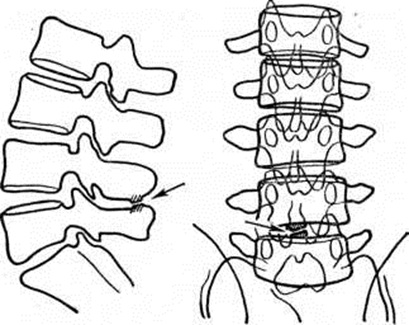

на их передних или задних поверхностях. Чем меньше радиус кривизны, тем сильнее выражен Лордоз На рентгенограмме в прямой проекции о степени Лордоз можно судить по величине расхождения переднего и заднего края тела I поясничного позвонка (рисунок 6). Иногда при выраженном Лордоз

чрезмерное сближение остистых отростков поясничных позвонков при гиперлордозе может привести к образованию между ними сустава и деформирующему остеоартрозу в нем (рисунок 7).